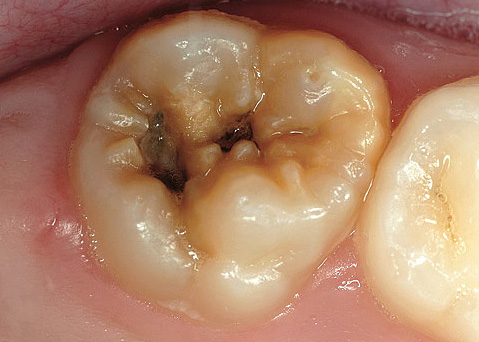

Una fotografia di un dente con una cavità profonda e cariata, che in qualsiasi momento può causare pulpite: